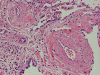

At scanning magnification (Panel A), the lung parenchyma is replaced by some coalescing fibrous nodules. The degree of involvement is variable at different fragments (Panel B and C). In the less affected areas, there are some fibrotic thickening of the septa (Panel C). In some areas, the changes are minimal and the pleural appear to be uninvolved (Panel D and E). In low to medium magnifications, these nodules of fibrosis contains a large number of hemosiderin laden macrophages (Panel F and G) admixed with fibrous tissue. The diagnostic tissue, however, is present in areas with increased cellularity. In these areas, there is a background of cells with a moderate amount of cytoplasm and bland nuclei. Some of these nuclei have kidney shape (arrow in Panel H). In some areas, many of the nuclei have a deep nuclear groove that resemble a coffee bean (arrow in Panel I). In the third type of areas, the nuclear grooving is not distinct (Panel J). Prominent eosinophilic infiltrations are almost always present. Immunohistochemistry on CD1a revealed many positive cells (Panel L). Also present in the specimen are multiple small blood vessels with thickened intima (Panel K). A Movat pentachrome stain demonstrates an internal elastic layer in these vessels and confirms that these are arteries (Panel M and N).

Pathologically, PLCH can be broadly divided into an early or cellular stage and a late or fibrotic stage. Demonstration of LCs is of critical importance for a correct diagnosis. The morphology of LCs is similar to LCH in other organs. LCs are characterized by a deep nuclear groove which lead to “coffee bean-shaped” or “kidney-shaped” nuclei. In most cases, the level of atypia and pleomorphism is low. A moderate amount of amphophilic to weakly eosinophilic cytoplasm is present. The cytoplasmic membrane is indistinct. Eosinophils and chronic inflammatory cells, varying from scant to abundant, are present. Except for a scant frankly pleomorphic cases, the level of pleomorphism and atypia is minimal to low. Eosinophilic abscesses with central necrosis may be present. Immunohistochemically, LCs are similar to their normal counter parts and are positive for CD1a and S100. At the ultrastructural level, Birbeck granules can be demonstrated. For most cases, the diagnosis can be established by histopathologic criteria but these additional features help to confirm the diagnosis.

In the early stage of PLCH, there are interstitial infiltrates composed of LCs, lymphocytes, macrophages, eosinophils, plasma cells and fibroblasts 4. The infiltrates enlarge to form nodules centered on the small airways. Brown pigmented macrophages (smokers macrophages) are present in and around the nodules. Eosinophils tend to localize at the innermost layer of the nodules, where LCs can be most easily found in the thickened interstitium. Associated patchy interstitial and airspace organization or respiratory bronchiolitis may be present. Other smoking related changes are also common. Cavitation often occurs within the nodules which represents either an airway remenant or de novo cavitation as the inflammatory infiltrate enlarges. There is centripetal replacement of the nodules by fibroblasts which produce the classic stellate lesions of PLCH. As the disease progresses, the number of nodules, cavitary granulomas and fibrotic scars increase in number.